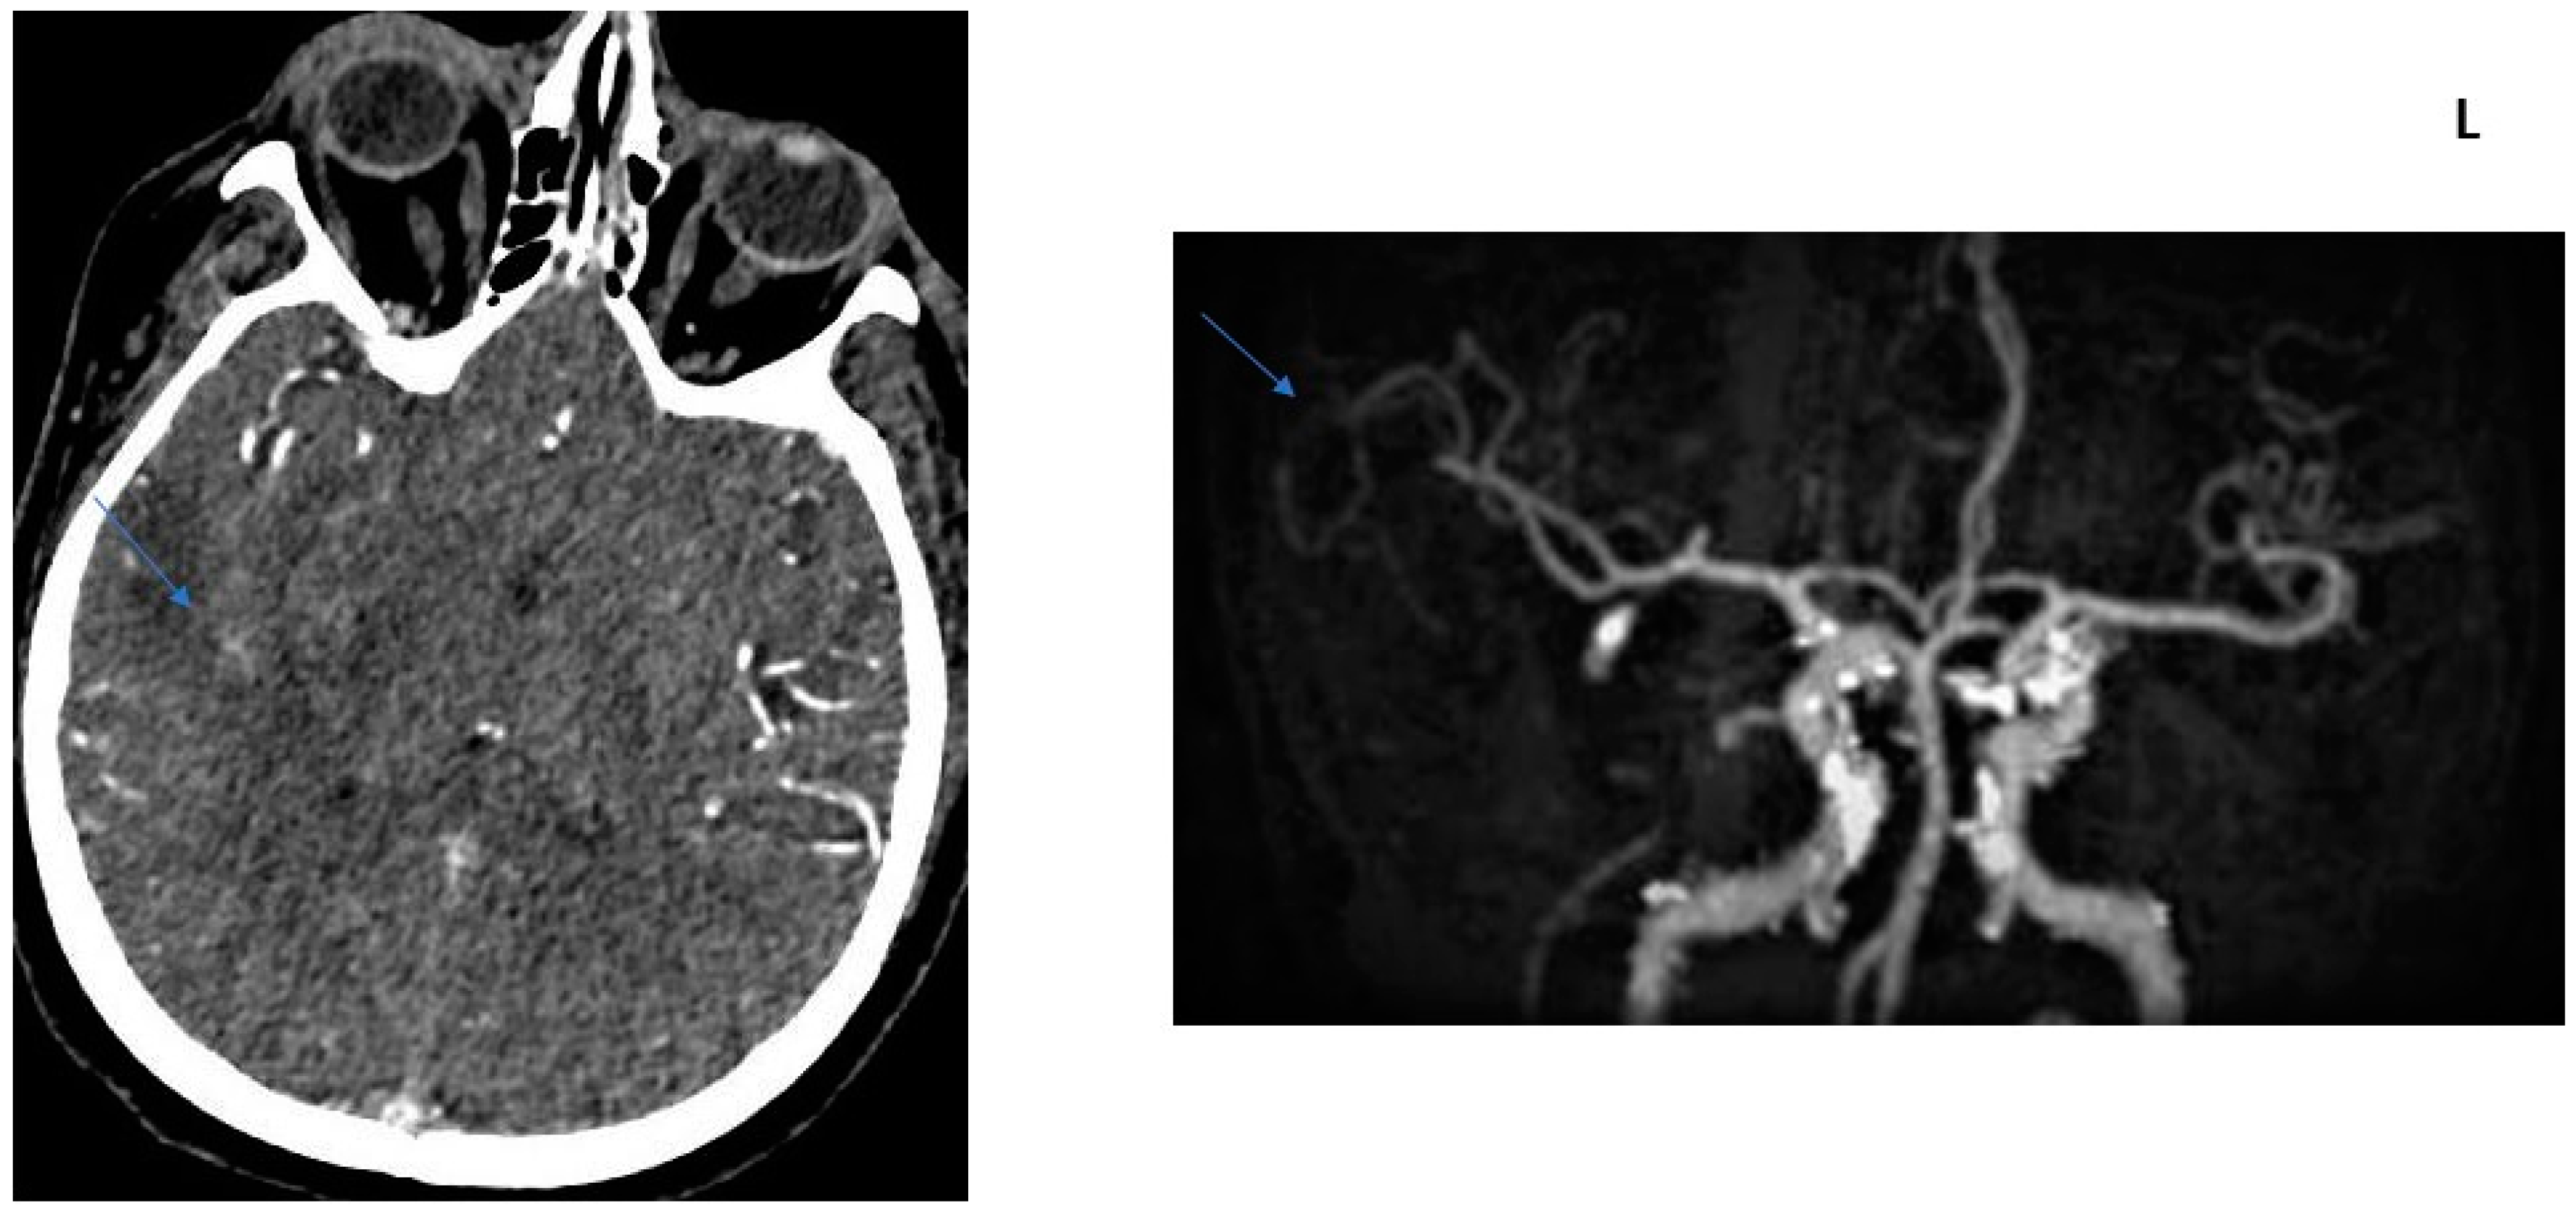

2.2. CT Protocol